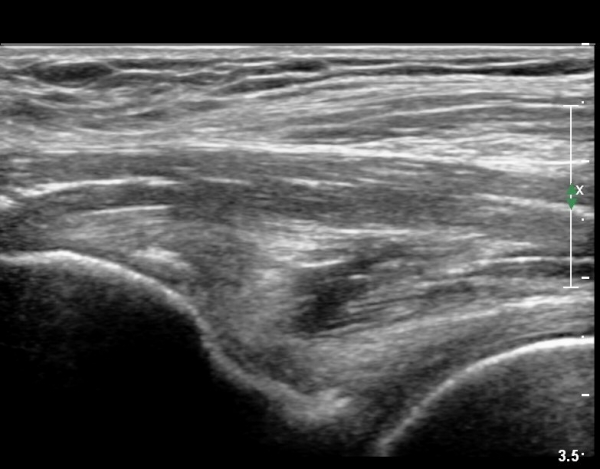

[¾ûµ¢ÀÌ] ÀüÇÏÀå°ñ±Ø °ß¿­°ñÀý(avulsion fracture of anterior inferior iliac spine)

Ç㸮¿Í ¾ûµ¢ÀÌ ÅëÁõ°ú ¿ìÃø ´Ù¸® ¶¯±è (±ÝÀÏ)

±ÝÀÏ ³Ñ¾îÁø ÈÄ ¸ñ, Ç㸮, ´Ù¸®ÀÇ ÅëÁõÀÌ ¹ß»ý. °ÉÀ» ¶§ ´Ù¸®°¡ ¾Èµé¸°´Ù.

´Éµ¿Àû SLR ¾ÈµÊ. ÀúÇ׿¡ ´ëÇÑ °í°üÀý ±¼°î°ú ¹«¸­ ½ÅÀü ½Ã ÅëÁõ°ú ±Ù¾àÁõÀ» º¸ÀÓ.